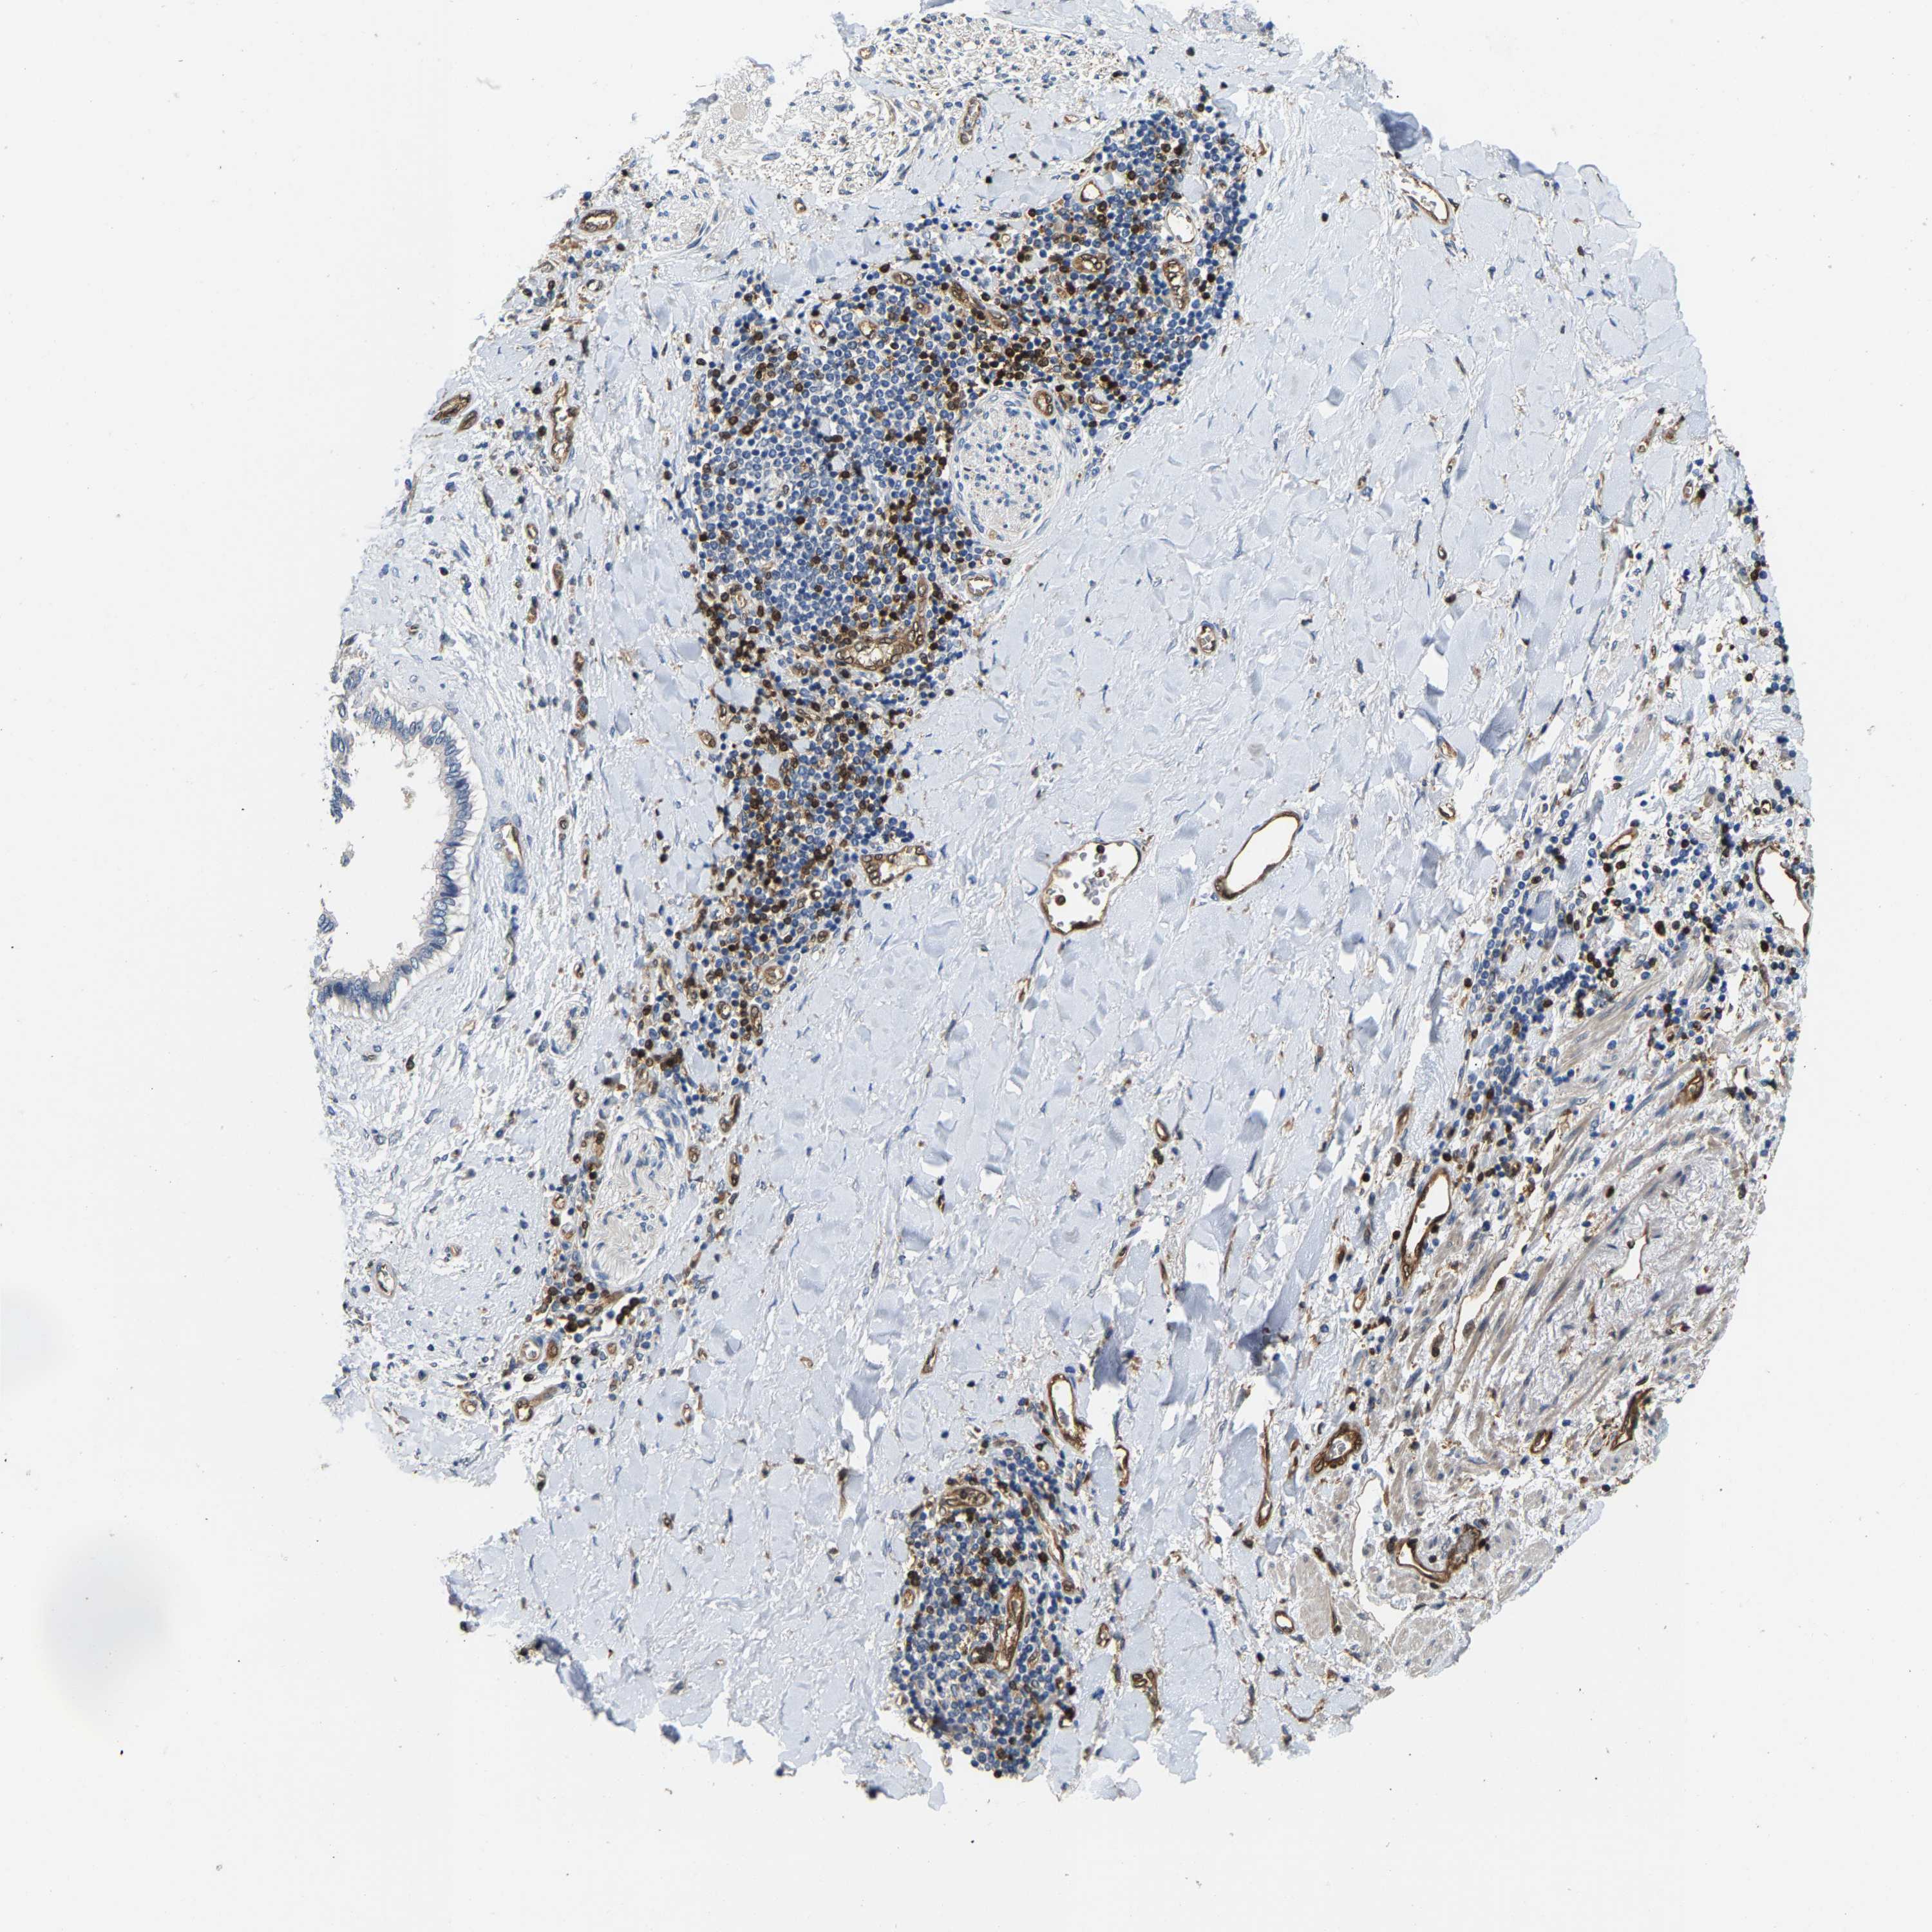

LIVER CANCER - Protein expressioni

A mouse-over function shows sample information and annotation data. Click on an image to view it in a full screen mode. Samples can be filtered based on level of antibody staining by selecting one or several of the following categories: high, medium, low and not detected. The assay and annotation is described here.

Note that samples used for immunohistochemistry by the Human Protein Atlas do not correspond to samples in the TCGA dataset.

Antibody stainingi

Antibody staining in the annotated cell types in the current human tissue is reported as not detected, low, medium, or high, based on conventional immunohistochemistry profiling in selected tissues. This score is based on the combination of the staining intensity and fraction of stained cells.

Each image is clickable and will lead to virtual microscopy that enables deeper exploration of all samples and also displays staining intensity scores, fraction scores and subcellular localization as well as patient and tissue information for each sample.

Antibody HPA020266

Antibody HPA020268

Staining

High

Medium

Low

Not detected

Intensity

Strong

Moderate

Weak

Negative

Quantity

>75%

75%-25%

<25%

None

Location

Nuclear

Cytoplasmic/membranous

Cytoplasmic/membranous,nuclear

Cholangiocarcinoma

Carcinoma, Hepatocellular, NOS